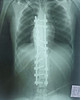

– Мы провели операцию по постановке многоопорной винто-стержневой системы: в позвонки последовательно введены специальные импланты – транспедикулярные винты, по вогнутой и выпуклой стороне деформации установлены отмоделированные титановые стержни. Перед нами стояли непростые задачи – выпрямление позвоночника и сохранение его функций – и мы с ними успешно справились. Маленькой пациентке предстоит реабилитация, после которой она сможет вернуться к полноценной жизни без боли и каких-либо ограничений, – пояснил Дмитрий Курдюмов.

После